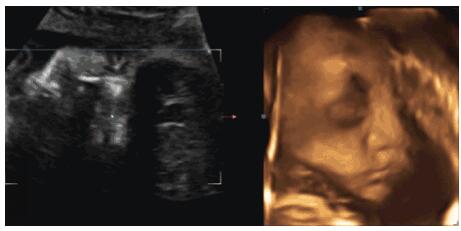

事实上,胎儿确实会在子宫内哭,而且已有不少的孕妇证实有时候会听到肚子里的宝宝哭。除此之外,据英国《卫报》报道,科学家首次使用4D超声波成像系统时发现,婴儿在出生前数周就已经会大哭不已了。有些胎儿的哭声比较微弱,像轻微的低鸣;有的胎儿的哭声比较有力,是大声抽泣的啼哭。而且,胎儿的啼哭声有些是可以在妈妈腹部听到的,有些则可以在妈妈的耳朵处听到。当然,并不是每个妈咪都能听到胎儿的啼哭,毕竟,声音太过微小,而不同的人对声音的敏感度也不同。1.孕妈妈肚里没东西吃了,胎宝宝会跟着肚子饿引起啼哭;2.胎宝宝已有自己的听力,能听到妈妈的心跳和外界的声音,如果准妈妈长时间处于嘈杂的环境、人声鼎沸及施工频繁等地方,胎宝宝也会被外面的声音所吓到,而引起啼哭;4.胎宝宝除了睡觉,其余时间都是在玩耍,实在无聊,就会把脐带当成玩具,围着脐带转圈圈,但有时候抓不到脐带,就会没有安全感而哭泣;5.如果子宫内羊水过少或供氧不足,也会引起胎宝宝的哭泣;6.胎宝宝身体发育异常,存在缺陷而导致身体不舒服。孕妈要重视胎儿的啼哭,如果孕妈咪听到了胎儿的啼哭,请务必前往医院检查,以确保胎儿的健康和安全。对于子宫里的胎宝宝来说,引起胎宝宝啼哭有很多原因,最重要的原因一定是胎宝宝在孕妈妈的子宫感到不适,可能是危险的预兆。

四维彩超是筛查胎儿畸形的重要手段。在这里,小编想要提醒准妈妈一句,四维彩超您预约了吗?如果还没有的话,请尽早预约哟!金猴宝宝+全面二胎,城阳玛丽妇儿医院四维彩超室外,每天轮流做四维的准妈妈都很多。